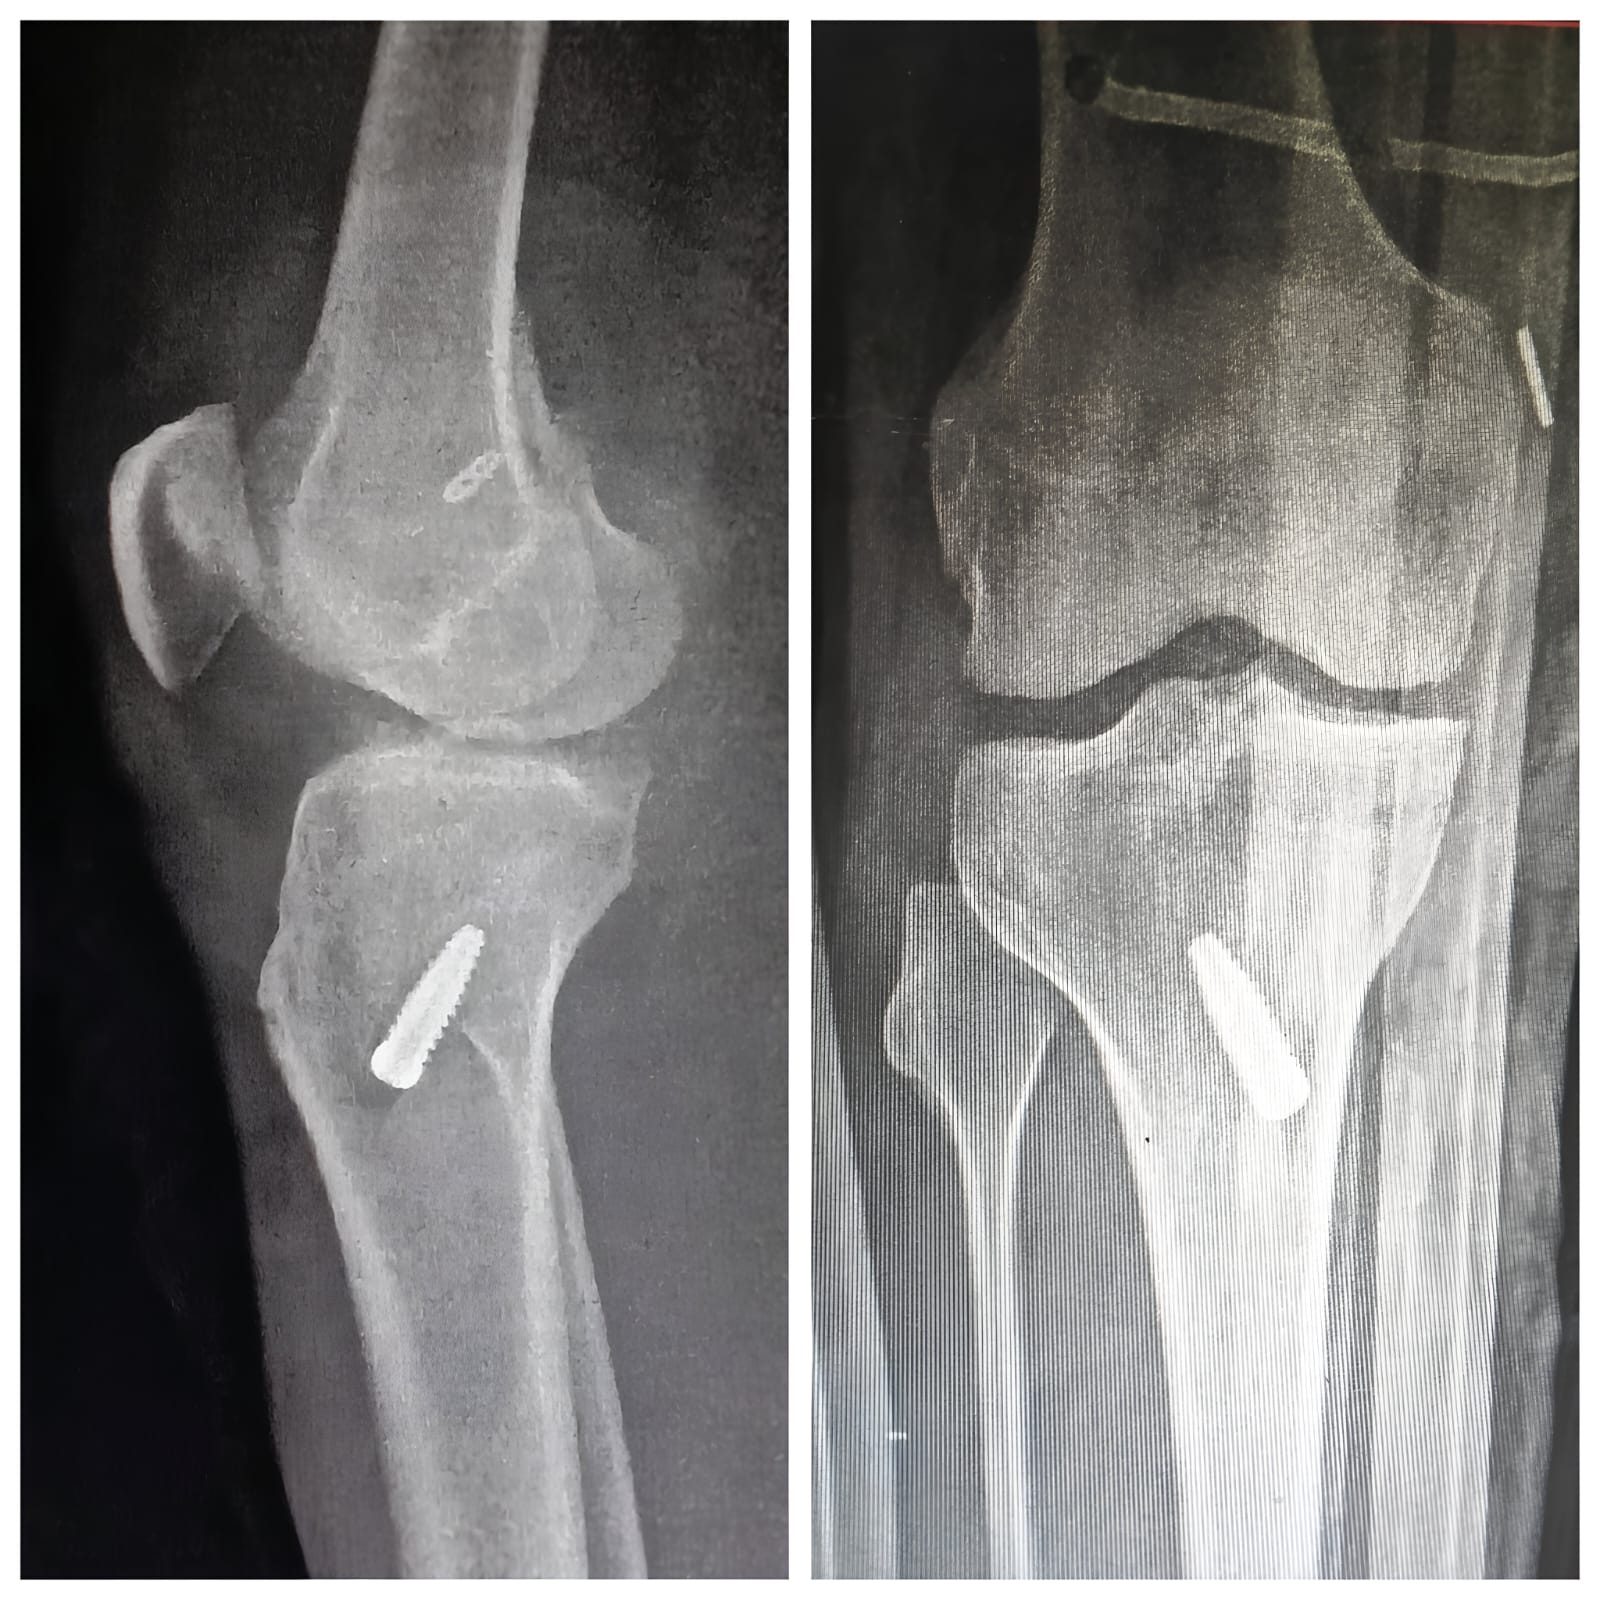

Sports Injury Surgery

Arthroscopic Surgery